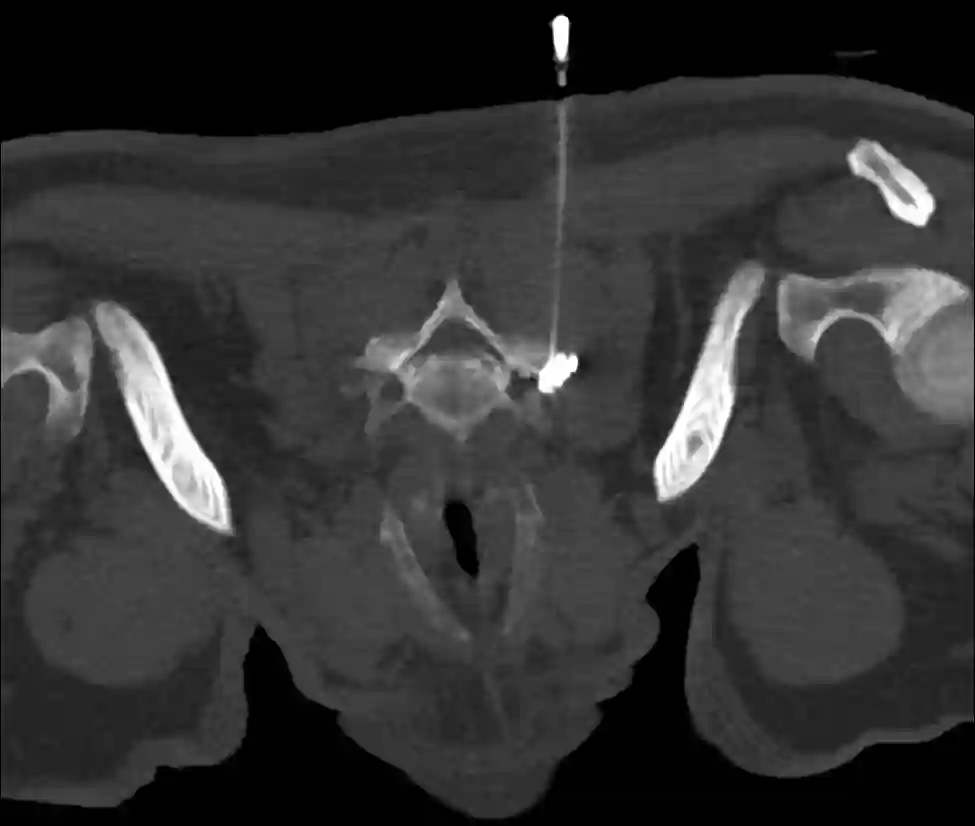

Bei einer Nervenwurzelinfiltration, oder auch Nervenblockade genannt, wird unter einer Bildgebung (Ultraschall, Durchleuchtung oder CT) eine Mischung aus Lokalanästhetikum, mit oder ohne Kortison direkt an die Nervenwurzel appliziert. Man unterscheidet zwischen einer therapeutischen und diagnostischen Infiltration.

- Durchführung einer Nervenwurzelinfiltration der Nervenwurzel C7 links mithilfe des CTs.